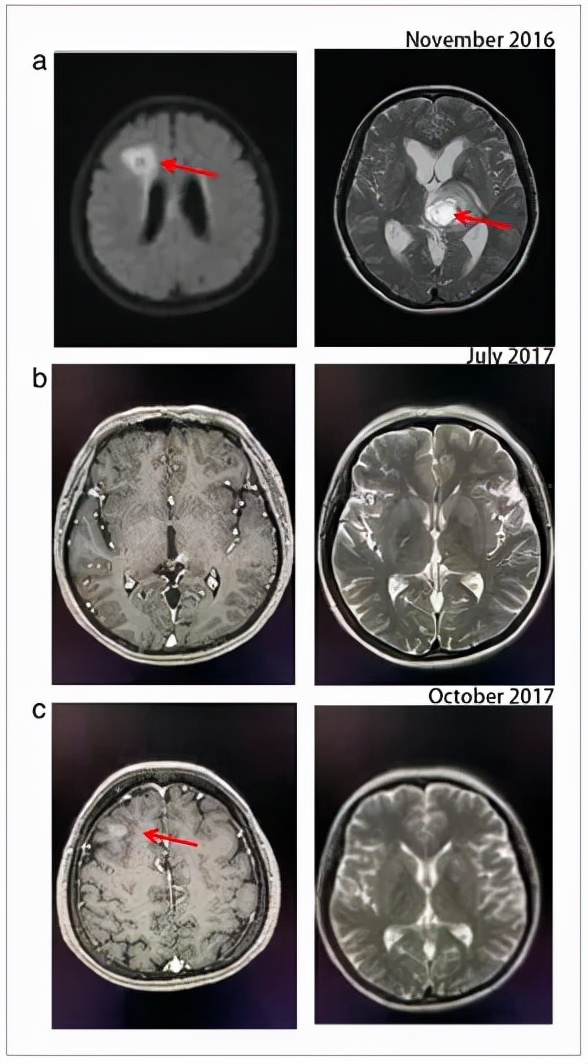

图注:患者转移性脑肿瘤病变的磁共振成像(MRI) (a)布加替尼治疗前(2016年11月) , (b)布加替尼缓解(2017年7月) , (c)布加替尼耐药(2017年10月) 。 红色箭头表示脑损伤 。

但患者因骨髓抑制、疲劳、恶心等不良反应 , 5个疗程后拒绝化疗 。 1月后患者出现意识障碍 , 脑MRI显示多发脑转移灶(左丘脑肿块0.7 x 0.8 cm , 额叶病变0.4 x 0.8 cm) 。 因此 , 患者需要二线治疗 。

治疗一天后 , 由于严重恶心 , 患者由克唑替尼改为布加替尼90mg 。 布加替尼治疗1周后 , 中枢神经系统症状意外消失 , 患者未出现任何不良事件 。 因此 , 布加替尼增加到180mg 。 1个月后 , 连续CT扫描显示原发病灶明显缩小(5.2×4.2 cm→2.0×1.0 cm) , 脑转移灶稳定 。

2017年7月 , CT扫描复查肺和脑转移灶显示病情稳定(SD) 。 而且 , 副作用是可以忍受的 。

布加替尼治疗持续了3个月 , 但在2017年10月 , CT扫描再次评估显示肺部病变进展和新的转移性脑损伤 。